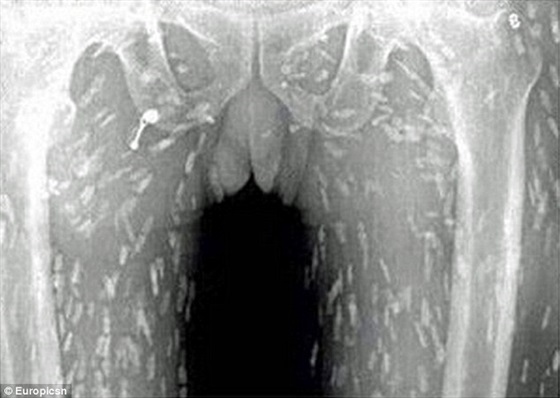

وكان الرجل ذهب إلى الطبيب يشكو من ألم في المعدة وحكة في الجلد، وكشفت الأشعة أن جسمه بالكامل أصيب بعدوى الدودة الشريطية .